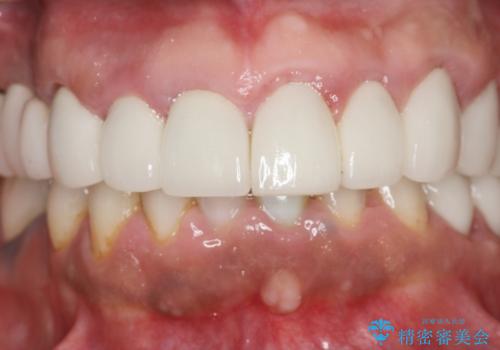

歯周外科を行い歯と歯槽骨・歯肉の関係を是正することで歯ぐきの状態を改善し、将来に亘り安定した歯周環境の維持を期待できるセラミック治療を実践します。

- 95.7万円(ジルコニアクラウン×6・仮歯×6・歯周外科)費用は治療当時の料金となります

歯ぐきが腫れたままの状態だと、違和感が生じるとともに常に炎症が存在する環境となってしまうので非常に好ましくない口腔内環境です。